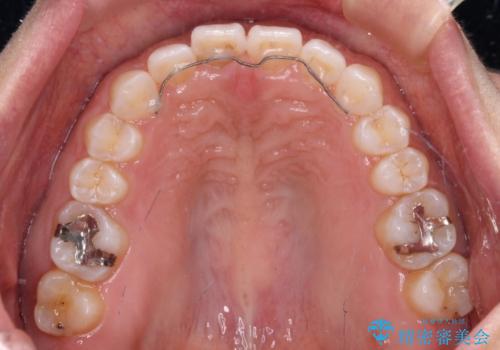

隙間の空いた前歯を閉じたい インビザライン矯正

- インビザライン

- 前歯の隙間を気にして来院された患者様です。

隙間、捻転ともに軽微でありましたが、下顎前歯の突き上げにより隙間ができていたため、インビザラインを用いて咬み合わせを改善しながら前歯の歯列を整えていくこととしました。

当初は1年程度で終えられると思いましたが、治療途中から装着時間が短くなったり、来院間隔が長期になったりとし、結果として4年半以上の治療期間となりました。

治療途中に上顎前歯は失活してしまいましたが、変色が顕著ではないため、経過を見ていくこととなりました。